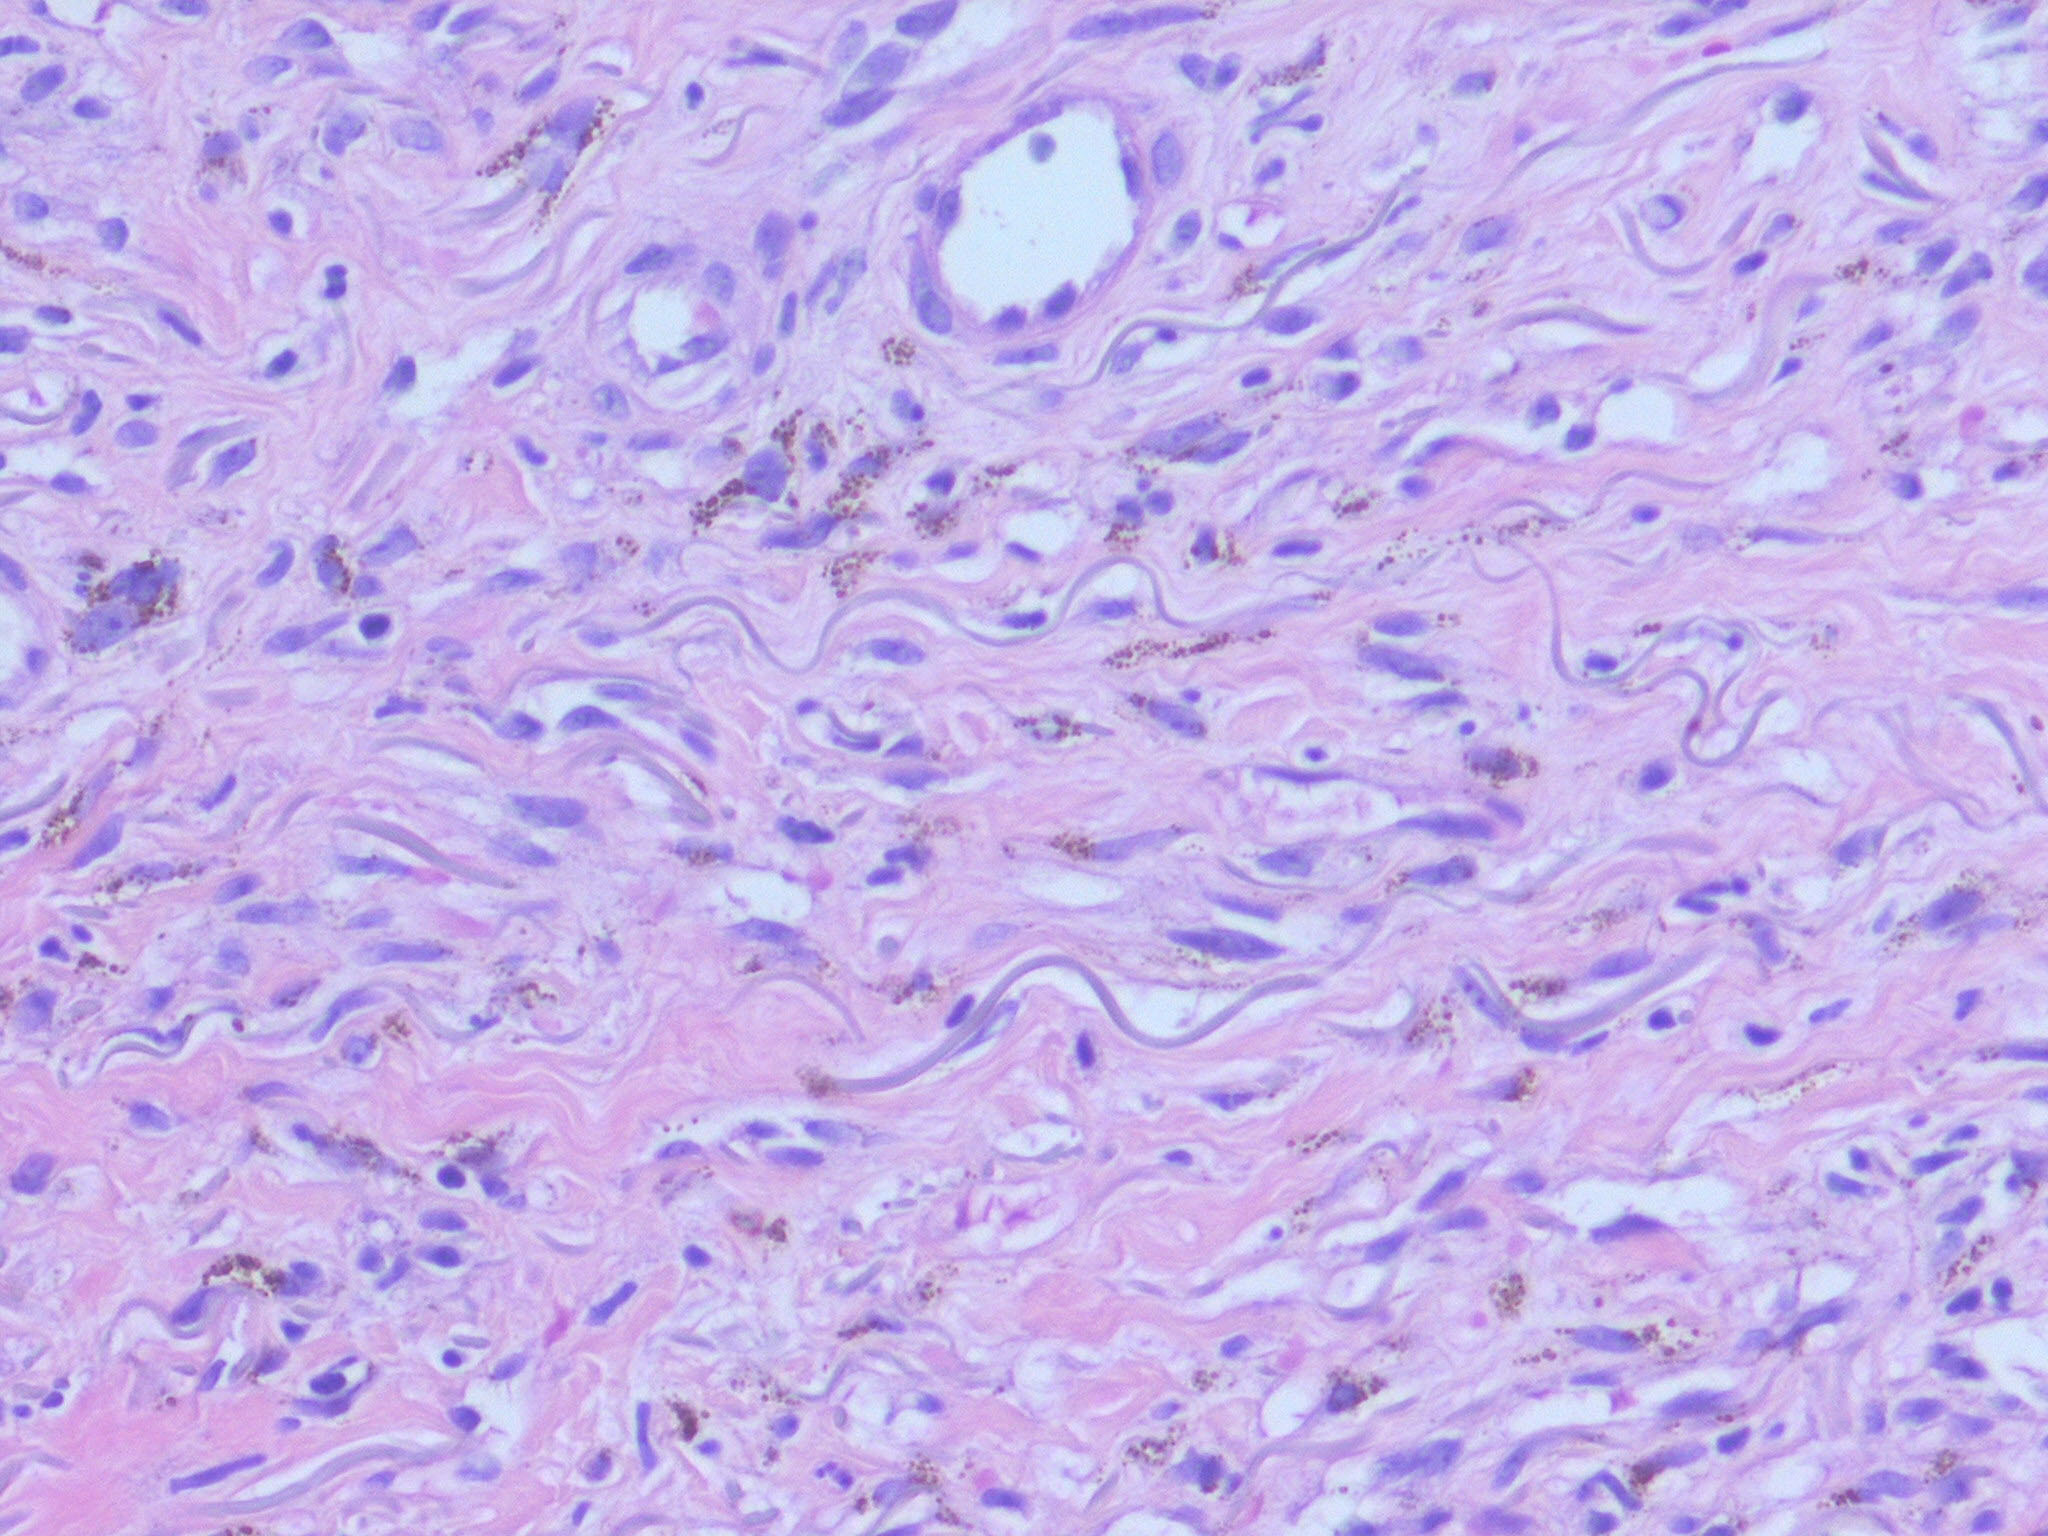

HISTOPATHOLOGY

The histopathology of KS is dependent on the stage of KS development. Early patch-like lesions exhibit rather discrete histopathologic changes, consisting mainly of an increase in the number of dermal vessels, outlined by slightly irregular endothelial cells (Fig. 128-5). These vessels, located mainly in the superficial dermis are parallel to the skin surface, are frequently slightly irregular, and may form bizarre slits and clefts. In the surrounding skin focal hemosiderin, deposits and extravasated erythrocytes can be found as well as a moderate inflammatory infiltrate. Important differential diagnoses of this stage include lymphangioma and granulation tissue.

The pathology of KS plaques is more characteristic and reveals extensive vascular proliferation at all levels of the dermis with multiple dilated and angulated vascular spaces dissecting the collagen leaving a spongy network of collagen tissue. A characteristic sign of KS papules is the presence of solid cords and fascicles of spindle cells arranged between the jagged vascular channels. This biphasic angiomatous and solid tumor morphology changes to a clear-cut sarcomatous morphology with progression of the disease.

Nodular lesions consist predominantly of spindle cells arranged in bundles and interlacing fascicles and interspersed, irregular, slit-like vascular spaces without endothelial linings. Advanced lesions may display pronounced pleomorphism, nuclear atypia, and mitotic figures. At the periphery of solid tumors, (lymph) angiomatous-like portions of KS with bizarre vascular lumina and intravascular and extravasated erythrocytes, as well as siderophages, may be preserved. Erythrocytes, which appear as eosinophilic globules, are trapped within the slits and clefts formed by the spindle cells and erythrophagocytosis are occasionally observed. As in all other stages of KS, a moderate inflammatory infiltrate consisting of lymphocytes, histiocytes, plasma cells, and, sporadically, neutrophils is regularly present.